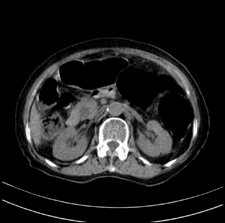

患者,女,75岁。腹痛,体黄5日,膝胸位时腹痛缓解。肝功能明日出来。彩超提示胆总管占位,未见血流信号。心电图提示s-t段改变。患者体质较弱,未能增强。

胆总管上段,腔内有软组织密度影 ,ct值36-44hu。大家看有没有胆管癌的可能。

典型胆总管多发结石;增强扫描前后ct值是否发生改变是鉴别结石与占位的依据。